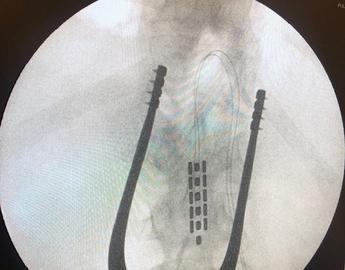

Ahmed Hussein shares his experience living with a spinal cord injury, and the impacts to his daily life regarding blood pressure management with nerve damage. Ahmed participated in the HEMO trial, run by the RESTORE Network at the Hotchkiss Brain Institute. The HEMO trial involved an implant on Ahmed's spinal cord, designed to monitor and modulate blood pressure fluctuations automatically, improving blood pressure symptoms such as hypertension, fainting, flushing, clot risk and more.

The RESTORE Network's Dr. Aaron Phillips co-led a groundbreaking research study recently published in Nature.